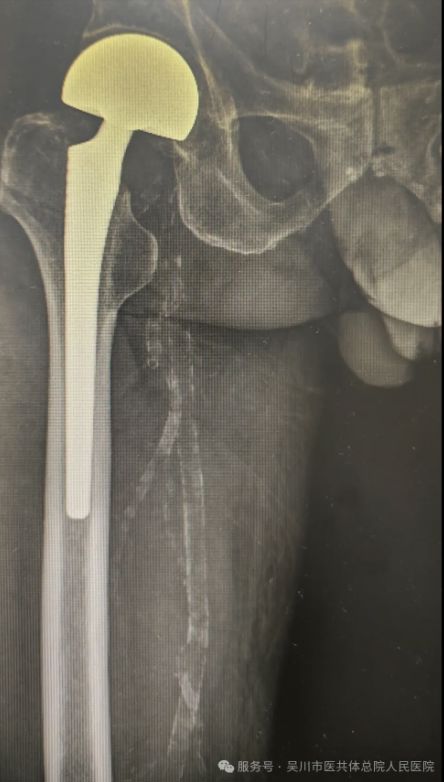

图片

九旬翁跨省寻医,名医妙手助行走

94岁的吴川籍老人王爷爷随家属在广西生活时不慎跌倒,随即入住南宁市某大医院后确诊为右股骨颈骨折,需要手术。考虑到老人年事已高,手术风险大,家属辗转打听后,决定带老人回到家乡吴川市,寻求我院骨外科三区曾维主任的治疗。

曾维主任团队共同评估老人身体状况后,制定了周密的手术方案,在做好充分术前准备后,成功为老人实施 “右侧人工股骨头置换术”。令人惊叹的是,术后第二天,王爷爷便能在医护人员指导下起床行走锻炼,家属激动地说:“没想到 94 岁高龄还能这么快恢复行走,曾主任团队的技术太厉害了,回家乡看病真是选对了!”